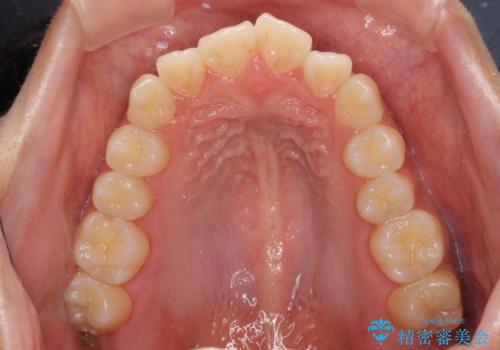

受け口と開咬を急速拡大装置とワイヤー装置で改善

- 前歯の開咬と、受け口による咬み合わせの悪さを気にして来院された患者様です。

上顎歯列が狭窄していたため、急速拡大装置により上顎骨を側方に拡大し、その後ワイヤー装置にて矯正治療を行うこととしました。